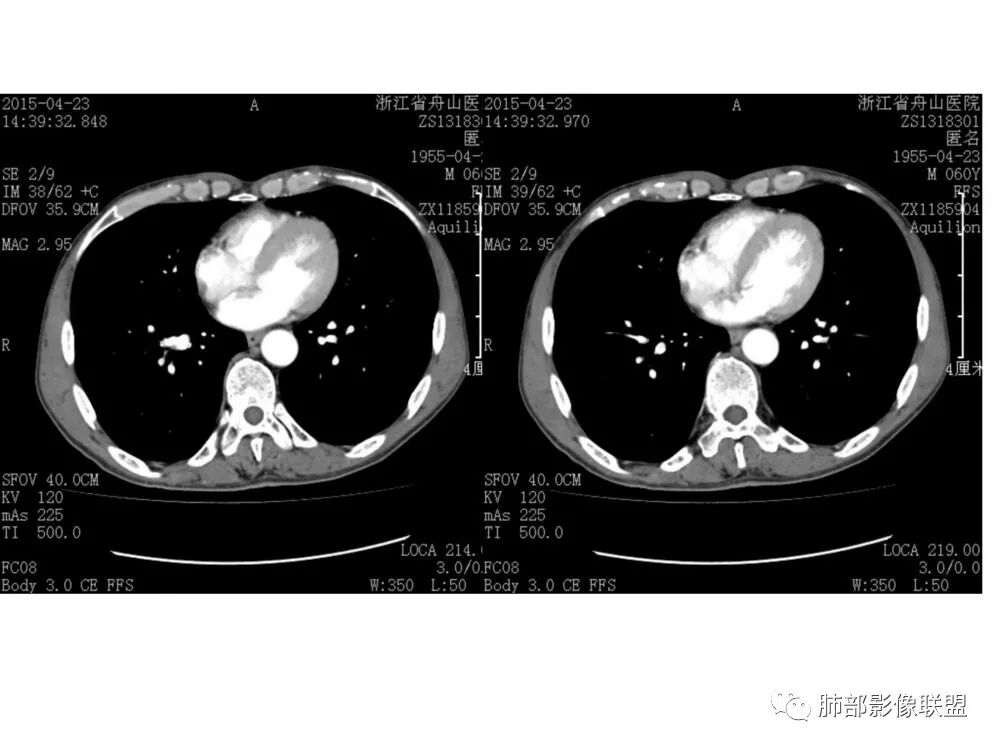

病理结果:鳞癌

1.鳞癌:多见于男性,抽烟史。可朝腔外生长,多为类圆形,偏心狭窄或环形增厚,常合并坏死,强化不等。生长在大支气管的鳞癌阻塞严重,周围会有明显阻塞性肺炎和肺不张。淋巴结转移相对较迟。

2.类癌:典型类癌绝大多数为中央型。对于成年人,更常见于女性。累及主、叶、段支气管,远端朝外侵犯,一般不是周围环形壁增厚;腔内外生长-冰山征;血供丰富、显著强化,可有钙化。

3.腺样囊性癌:是一种低级别恶性肿瘤,在气道恶性肿瘤中发病率居第2位。腺样囊性癌起源于气管黏液腺,好发于气管后壁软骨和膜部连接处,这与该部位黏液腺较多有关,肿瘤可呈息肉样或结节样突入,宽基底,管壁局部浸润性增厚,也由气管黏膜下方沿管壁长轴浸润生长,至管壁不同程度增厚及相应管腔狭窄,肿瘤强化不明显。

4.粘液表皮样癌 :多 40岁以下, 与吸烟无关 好发于主支气管远段,叶、段支气管,腔内结节,可分支状,轻度强化,常伴阻塞性肺炎/不张,粘液栓(密度低)